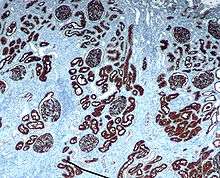

Neprilysin immunohistochemical staining of normal kidney.

Neprilysin is also associated with other biochemical processes, and is particularly highly expressed in kidney and lung tissues. Inhibitors have been designed with the aim of developing analgesic and antihypertensive agents that act by preventing neprilysin's activity against signaling peptides such as enkephalins, substance P, endothelin, and atrial natriuretic factor.[12][13]